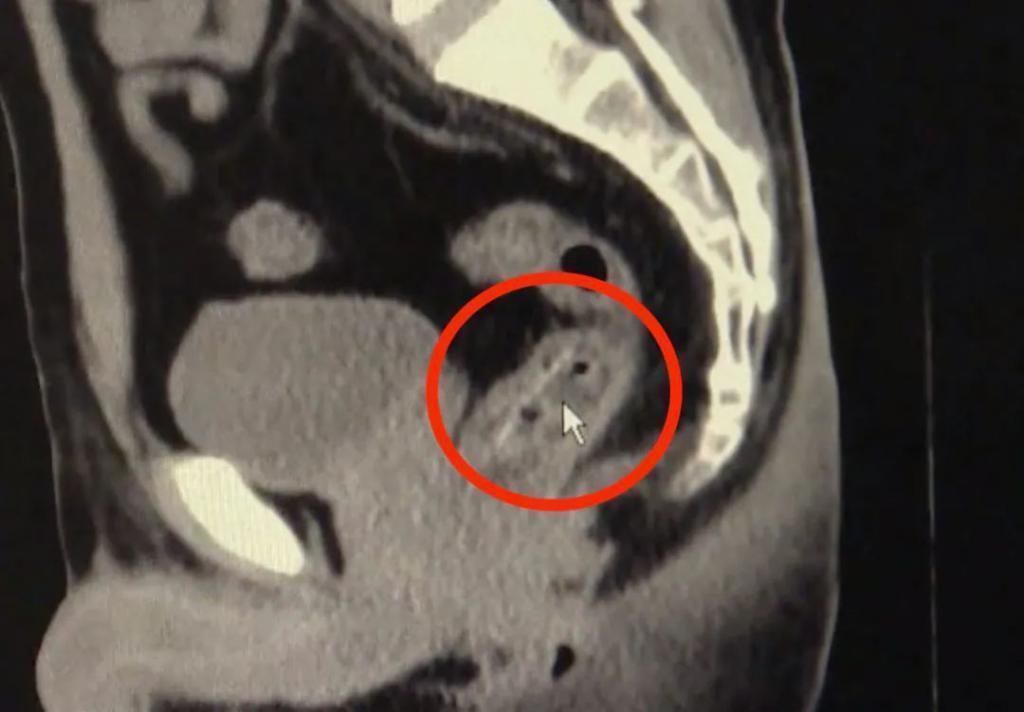

医生检查后

也吓了一跳

原来,一根鱼骨

竟然卡在了他的直肠腔内

医院为张先生进行直肠异物取出术

终于,从张先生肛门处

取出了一条长约3厘米的鱼骨

目前,张先生恢复情况良好